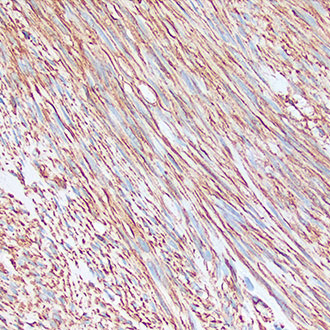

Vimentin

Vimentin -